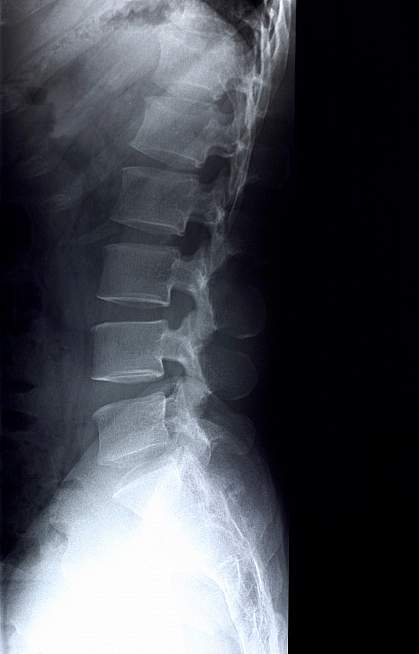

Bones are made of a mineral and protein scaffold filled with bone cells. Bone is continually broken down and replaced. When the rate of bone loss outpaces the rate of replacement, bones weaken, eventually leading to osteoporosis and increased risk of fracture. More than 40 million people nationwide either have osteoporosis or are at increased risk for broken bones because of low bone mineral density (osteopenia).

The researchers first combined data from 17 different studies involving more than 80,000 people across North America, Europe, East Asia and Australia. They looked across the genome for genetic variants associated with bone mineral density of the femoral neck and lumbar spine. The researchers found 96 independent variations from 87 genomic regions.